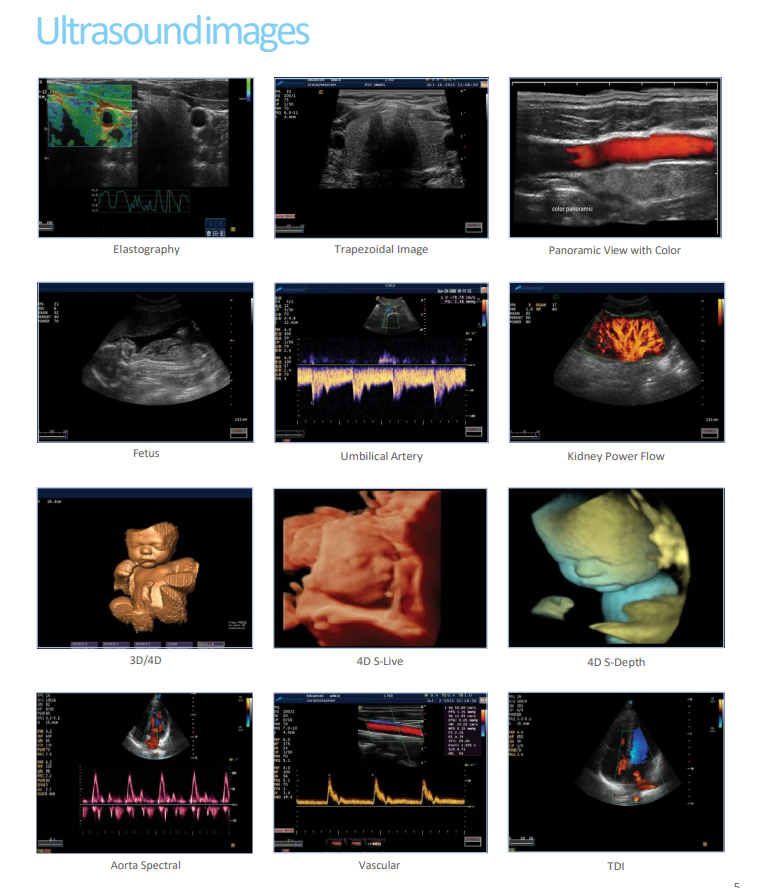

3D/4D imaging, FreeHand 3D

Elastography Imaging

Modes:THI,PIH,Color,PDI,DPDI,PW, Simult,SteerM,Color

M, TDI, CW, B

Trapezoidal imaging